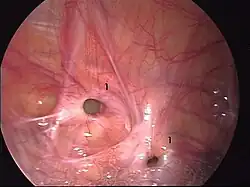

Ryc. 2 Śródoperacyjny widok kanału pachwinowego. 1. kanał pachwinowy 2. powrózek nasienny 3. naczynia nabrzuszne dolne.

Przepuklina pachwinowa skośna rozpoczyna się w pierścieniu głębokim. Kanałem przepukliny jest kanał pachwinowy. Ujście znajduje się pod skórą w okolicach moszny w tzw. pierścieniu powierzchownym[3] (Ryc. 2 i 4).